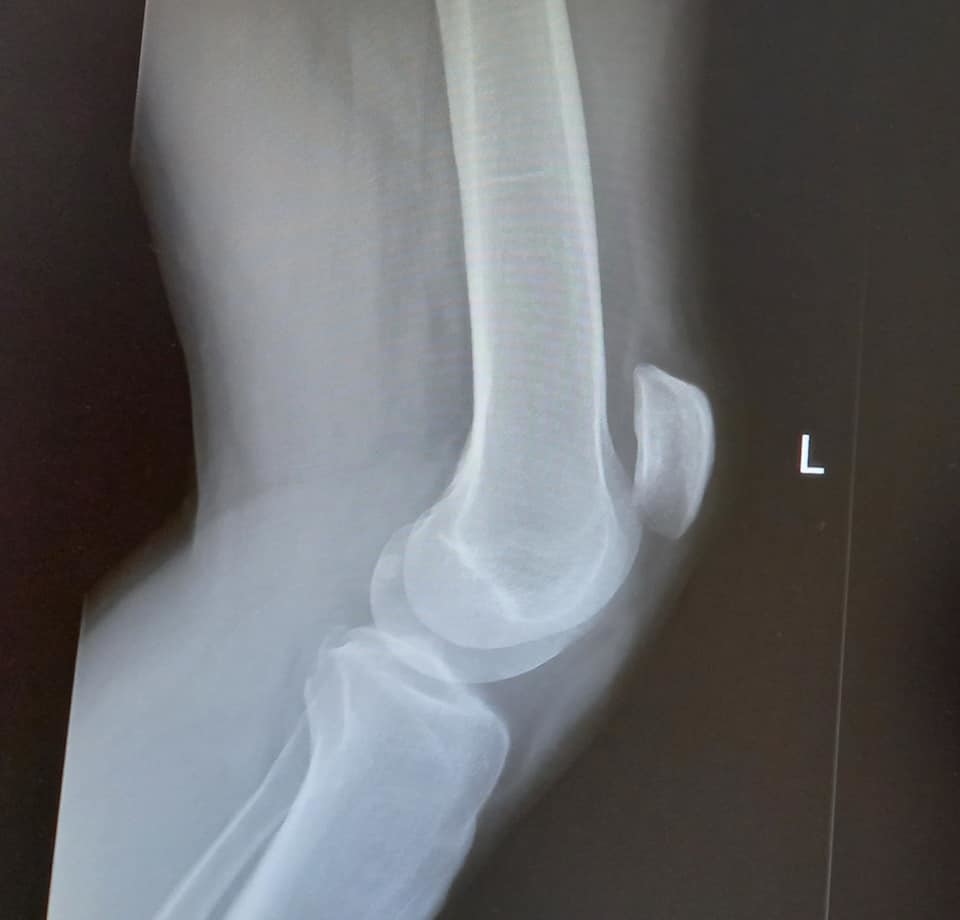

O antes e o depois da ancoragem da carroçaria, segundo as novas normas de segurança. Falta ainda afinar a barra anti-aproximação para que a suspensão - agora de duas vias - trabalhe firmemente... ![]()